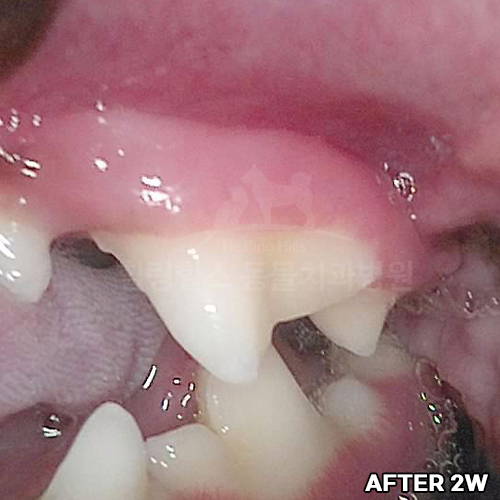

[치주치료 후 5개월 경과]